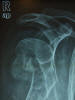

Fractura impactada de húmero .